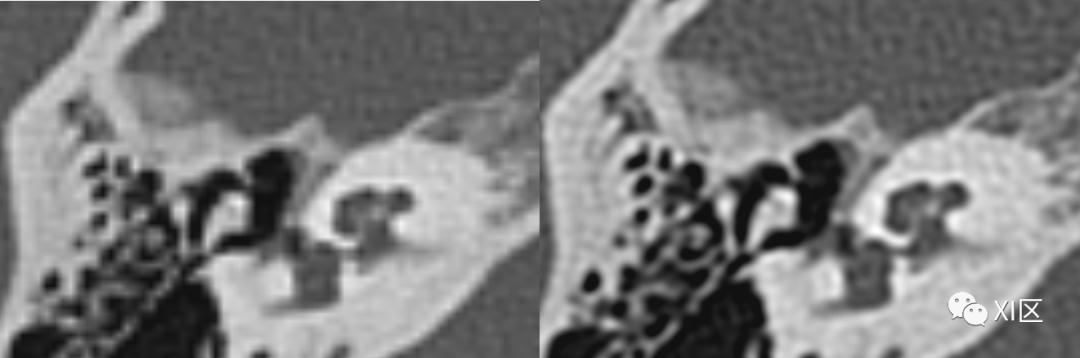

ZUHR和第三代双源UHR技术比较。第一代双源(A),第二代双源(B)和第三代双源(C)内耳图像比较。注意使用0.4x0.5 mm的小焦点第三代双源UHR模式图像质量显著改善。层厚均为0.4 mm。

Initial results of a new generation dual source CT system using only an in-plane comb filter for ultra-high resolution temporal bone imaging[J]. European Radiology, 2015, 25(1):178-185.

SOMATOM Force CT常规扫描重建0.6 mm(192x0.6 mm)图像(左)与IVR重建0.6 mm(576x0.6 mm)图像(右)比较。使用IVR技术的图像内耳细微结构显示更清晰。